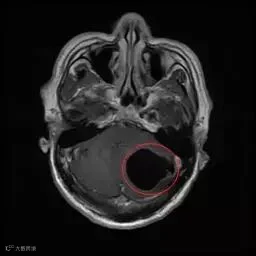

X光片显示刘先生

术前头部MR

左侧小脑半球内一较大的囊性占位

压迫小脑、脑干

为囊虫病变

“黑色空洞”部分即为囊虫病灶

▼